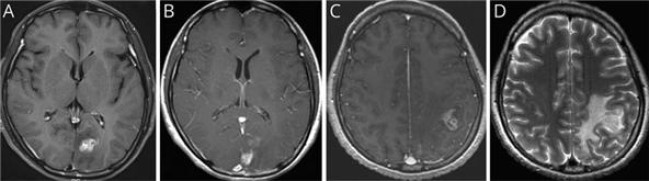

이번 연구는 서울대병원에 내원한 40대 여성 환자를 대상으로 이뤄졌다. 환자는 심한 두통과 구토 증세로 병원을 방문했으며, 초기 뇌 자기공명영상(MRI)에서 좌측 후두엽에 불규칙하게 조영된 종양성 병변이 발견돼 뇌종양이 의심됐다. 의료진은 수술을 권유했지만, 환자는 증상이 일시적으로 호전되자 치료를 거부하고 퇴원했다.

7개월 후 환자는 다시 극심한 두통과 전신 발작으로 병원을 방문했다. 후속 MRI에서 병변이 좌측 후두엽에서 좌측 두정엽으로 이동한 것이 확인됐고, 이 병변 이동은 스파르가눔증의 대표적인 진단 단서가 됐다.